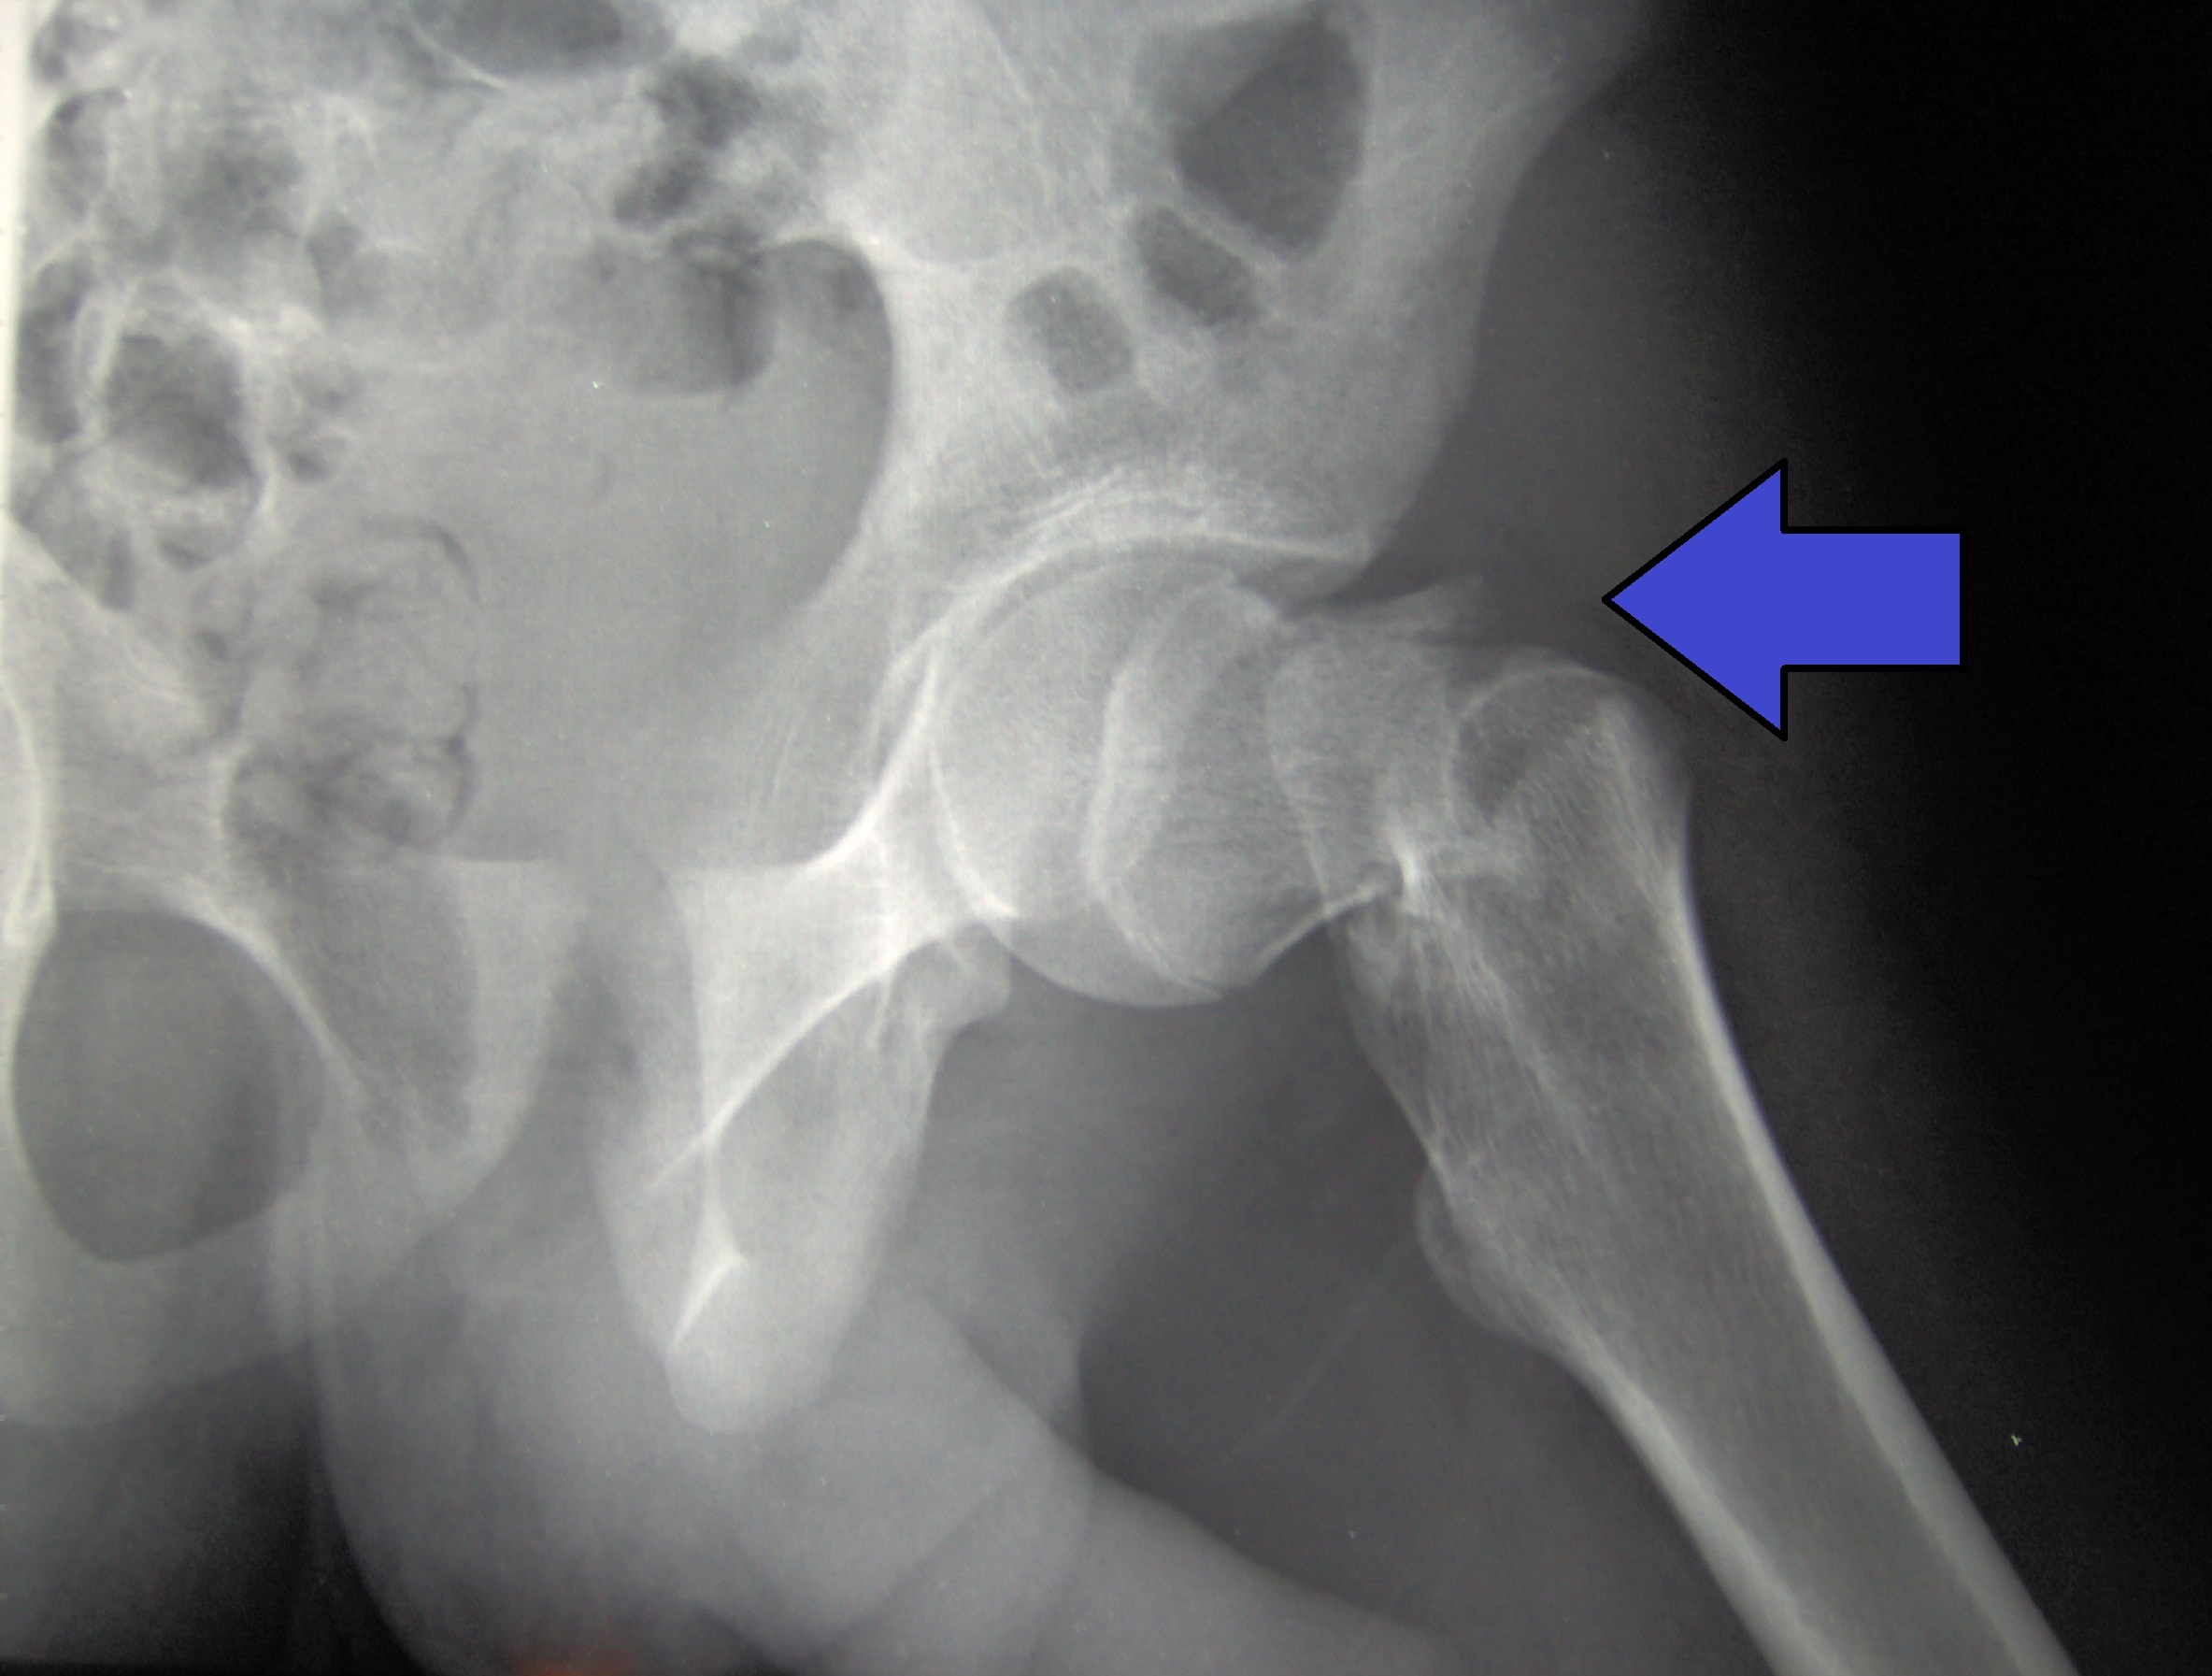

Booyabazooka, CC BY-SA 3.0 <http://creativecommons.org/licenses/by-sa/3.0/>, via Wikimedia Commons